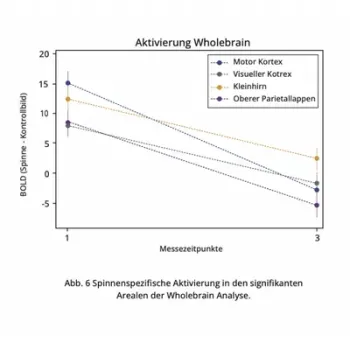

"After repeated use (Total 5 hours per personon average, spread over 4 weeks) of the Mind Switch® Fear & Phobia App, a strong reduction in the response to images of spiders was demonstrated in brain areas usually strongly associated with phobias: In the right amygdala, average activity was reduced by 117%, and in the left amygdala by an average of 145%. In the visual areas of the brain, there was a reduction from 8 units to an average of -1.6 units, in somatosensory-motor regions from 15.1 to - 2.8 units, in the parietal lobe from 8.6 to -5.3 units, and in the cerebellum from an average of 12.2 to 2.7 units. In summary, these results clearly indicate that in people suffering from phobias, a significant reduction in brain activity is observed with repeated use of the app. And this is in brain areas associated with anxiety."

Whole brain analysis

Whole brain analysis